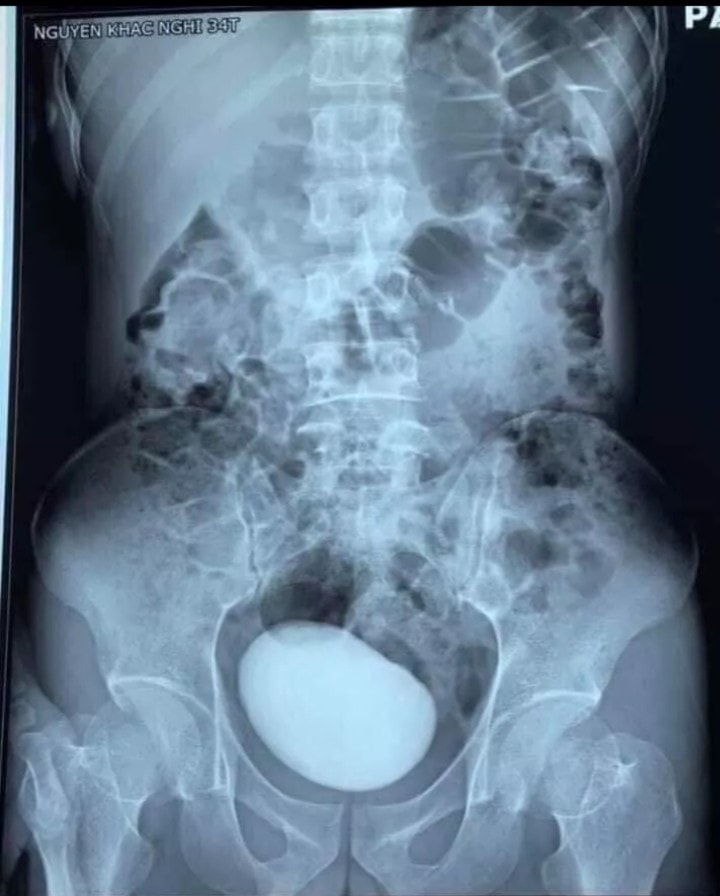

สาวเวียดนามปวดท้องรุนแรง ถูกหามส่งโรงพยาบาล แพทย์ผ่าตัดพบนิ่วในกระเพาะปัสสาวะ ก้อนโตสุดสะพรึง หนักเกือบครึ่งกิโลกรัม

รายงานเผยว่า หญิงรายดังกล่าวถูกนำตัวส่งห้องฉุกเฉินของโรงพยาบาลฟู้บิ่ญ ในจังหวัดท้ายเงวียน ของเวียดนาม ภายหลังจากเธอมีอาการปวดท้องอย่างรุนแรง ผลการตรวจซีทีสแกนพบว่า เธอมีก้อนขนาดใหญ่อยู่ในช่องท้อง แพทย์จึงดำเนินการผ่าตัดฉุกเฉิน

ผลปรากฏว่า แพทย์พบนิ่วในกระเพาะปัสสาวะของเธอ มันมีลักษณะแข็งเป็นก้อนหินขนาดใหญ่ เส้นผ่านศูนย์กลางยาวกว่า 10 เซนติเมตร และมีน้ำหนักมากถึง 400 กรัม ซึ่งทางโรงพยาบาลไม่ได้ให้ข้อมูลรายละเอียดเกี่ยวกับเคสนี้ แต่ภาพถ่ายของมันที่ถูกเผยแพร่ออกมาสร้างความประหลาดใจไม่น้อย และนับว่าเป็นเคสที่หาพบได้ยาก